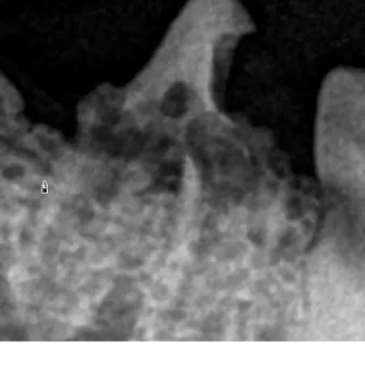

Have a challenging case? Simply email your dental radiographs along with a brief history, and receive a detailed review and consultation. I will assess the imaging, identify underlying pathology, and provide practical, case-specific treatment recommendations to help guide your next steps with confidence. Email x-rays to